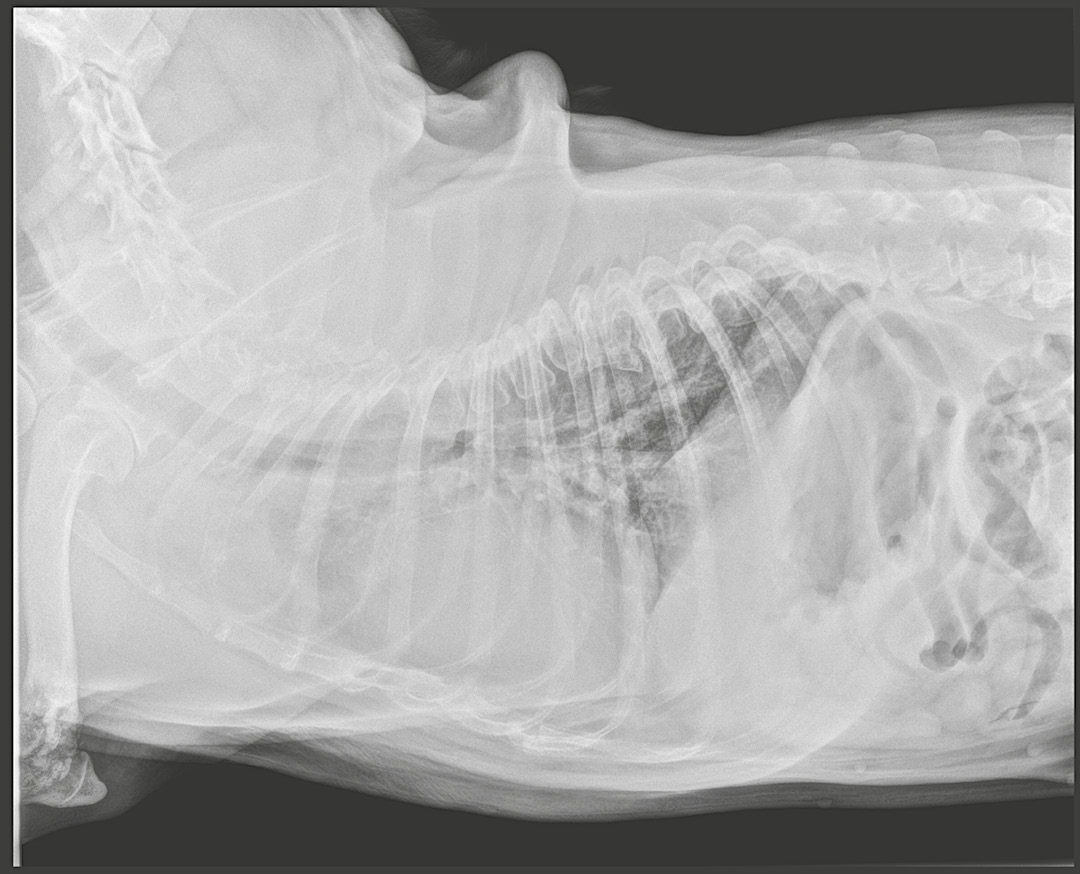

En las radiografías torácicas lo más relevante es la presencia de cardiomegalia con una silueta cardiaca de aspecto globoso, patrón bronco-intersticial difuso a nivel pulmonar y desplazamiento de la tráquea hacia el lado derecho (imagen 2).

Imagen 2. Radiografías latero-lateral derecha y ventro-dorsal del paciente en el momento del diagnóstico.